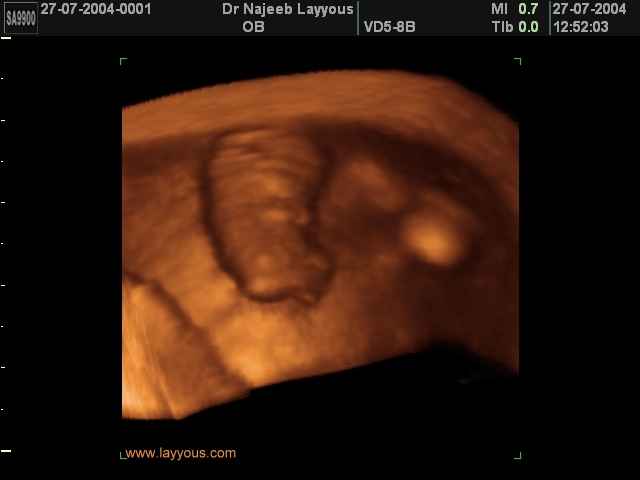

3D First Trimester Ultrasound Scan Photos ( Early Pregnancy Ultrasound Photos ) | Dr N Layyous

3D First Trimester Ultrasound Scan Photos